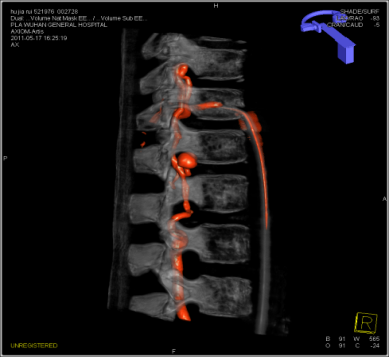

DynaCT双容积成像可以对不同容积影像如支架、弹簧圈、血管等同时显示,指导医生对支架释放、治疗预后进行评估。

血管,介入材料,骨骼的双容积成像,分辨三维空间中的位置关系,以及动静脉双血管的融合。

syngo Dyna4D展示特定时间点上的3D图像,对于脑血管畸形、血管瘤、动静脉瘘的结构、位置,并测量尺寸、分析供血动脉和引流静脉等。